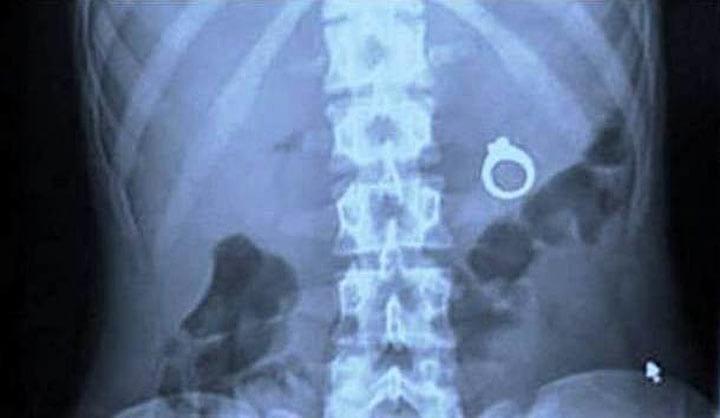

18. Он хотел сделать предложение девушке и спрятал кольцо в молочный коктейль. Но что-то пошло не так…